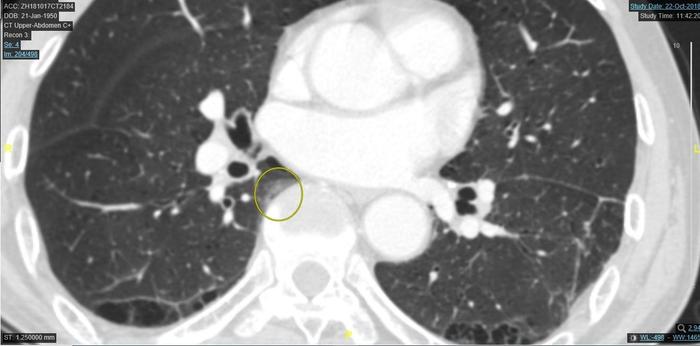

三、病例3、脊柱旁的肺突入纵隔处的肺磨玻璃样影,

脊柱旁的肺突入纵隔处的肺磨玻璃样影,一般是良性的。

上图圆圈处的脊柱旁的肺突入纵隔处的一个肺磨玻璃样影。不是圆形或椭圆形。这个地方有些病人会有一个磨玻璃样影子。本图的磨玻璃样影比一般病人影子深一倍以上,一般病人此处的磨玻璃影子比此图浅得多。